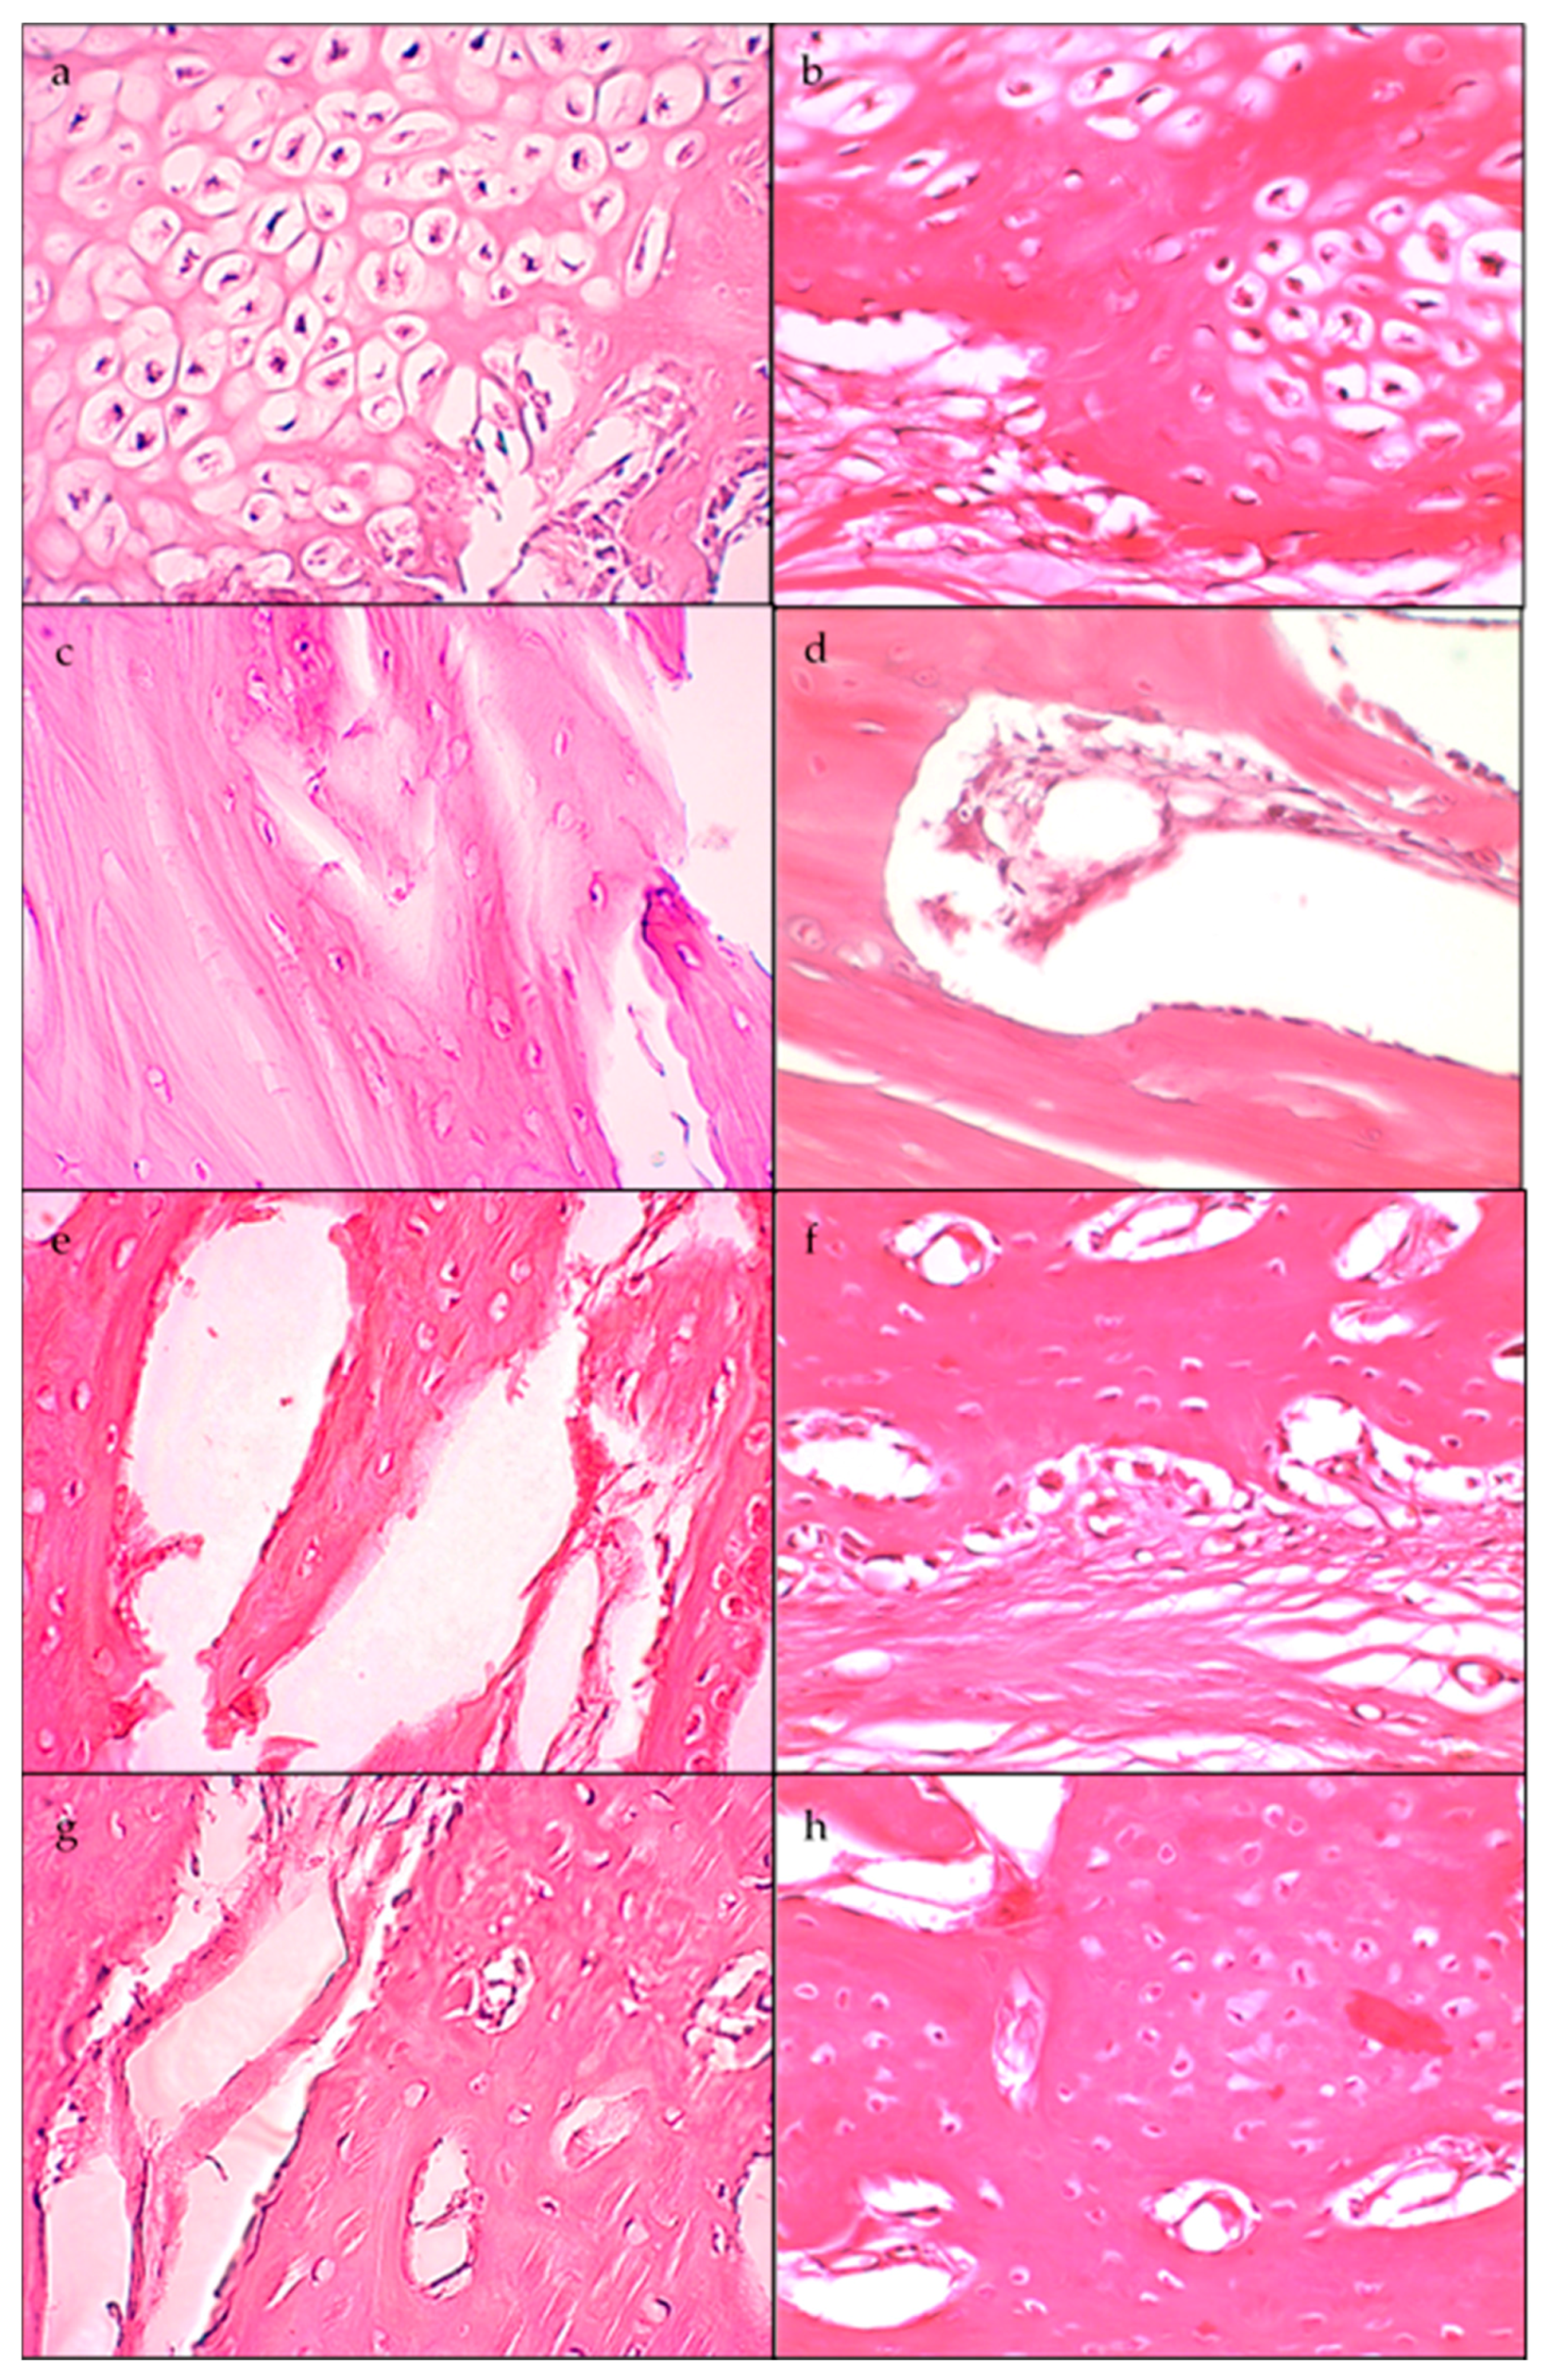

2.3. Histological Analysis

| Days | Average Osteoblasts | Average Osteocytes | ||

|---|---|---|---|---|

| Standard Membrane | High Membrane | Standard Membrane | High Membrane | |

| 20 | 960 (10 fgm) | 310 (10 fgm) | 580 (10 fgm) | 940 (10 fgm) |

| 30 | 50 (4 fgm) | 1400 (10 fgm) | 270 (4 fgm) | 1100 (10 fgm) |

| 40 | 1000 (10 fgm) | 300 (10 fgm) | 680 (10 fgm) | 400 (10 fgm) |

| 60 | 33 (10 fgm) | 310 (10 fgm) | 360 (10 fgm) | 800 (10 fgm) |